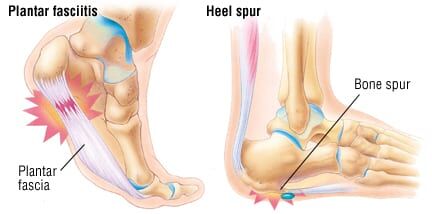

Heel Pain Causes and Treatment clearance, Heel Pain Causes Diagnosis Treatment clearance, Foot Pain Causes Treatment clearance, Plantar fasciitis treatment symptoms and causes healthdirect clearance, Plantar fasciitis Symptoms and causes Mayo Clinic clearance, Heel Pain Plantar Fasciitis is a common and Painful Condition clearance, Plantar Fasciitis Causes Symptoms Treatments and More clearance, Heel Pain causes and treatment plantar fasciitis diagnosis and treatment clearance, All About Heel Spurs Causes Treatments and Prevention Westfield Foot and Ankle LLC clearance, Plantar Fasciitis Symptoms Causes Treatment Options clearance, Plantar Fasciitis The Literal Pain In Your Heel Orthopaedic Associates of Duluth clearance, Pain in the Back of the Heel Causes and Treatment clearance, Heel Pain Types Symptoms Causes and Treatment clearance, Heel Pain Plantar Fasciitis Complete Physio clearance, Causes of Heel Pain clearance, Patient Basics Heel Pain 2 Minute Medicine clearance, Heel Pain 4 Major Causes and how to prevent them clearance, That Pain in Your Feet May be Plantar Fasciitis clearance, Heel Pain A Step Ahead Foot and Ankle Care clearance, Suffering With Plantar Fasciitis Heel Pain Symptoms Treatment clearance, Heel Pain Treatment Foot Doctor Toronto Ontario M3H 3S3 clearance, Pinpoint Your Foot Ankle Pain OrthoNebraska clearance, Heel Fat Pad Syndrome Symptoms Causes Treatment clearance, Heel Pain Podiatrist In Sterling Heights MI Advanced Foot Ankle Wound Care clearance, Plantar Fasciitis Treatment Symptoms Causes Prevention PediFix clearance, What s Causing My Heel Pain Quick Pain Relief Performance Health clearance, Why does top my heel hurt clearance, Heel Pain Treatment Nassau County Podiatrist clearance, Plantar fasciitis Information Mount Sinai New York clearance, Causes of Heel Pain clearance, Plantar Fasciitis and Foot Pain clearance, 4 Exercises to Relieve Heel Pain Kelly L. Geoghan DPM Podiatrist clearance, Why Does My Heel Hurt Syracuse Podiatry Dr. Ryan D Amico clearance, Dealing With Foot Problems Lucky Feet Shoes Has Hundreds of Styles to Help Ease Your Foot Pain clearance, Heel Spurs Causes Solutions Diagnostic Foot Specialists clearance.